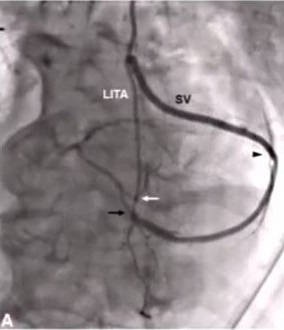

Can a Single ITA Composite Graft Adequately Supply the Heart?

Marc Ruel